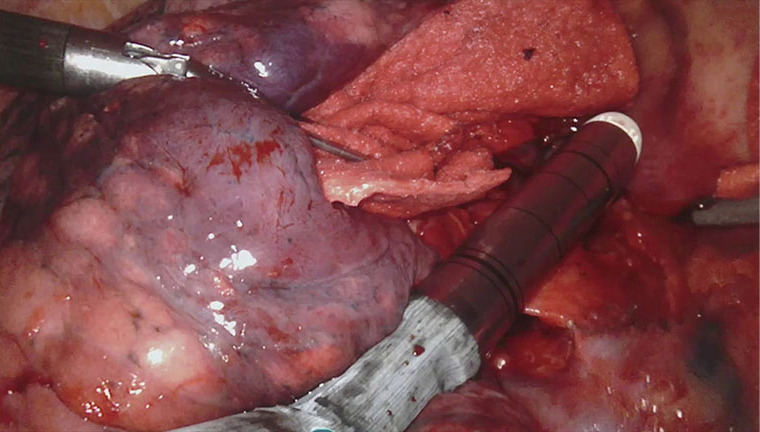

Figure 6.

Right upper lobe vein transected with robotic stapler.

Figure 7.

Boyden trunk transected with robotic stapler.